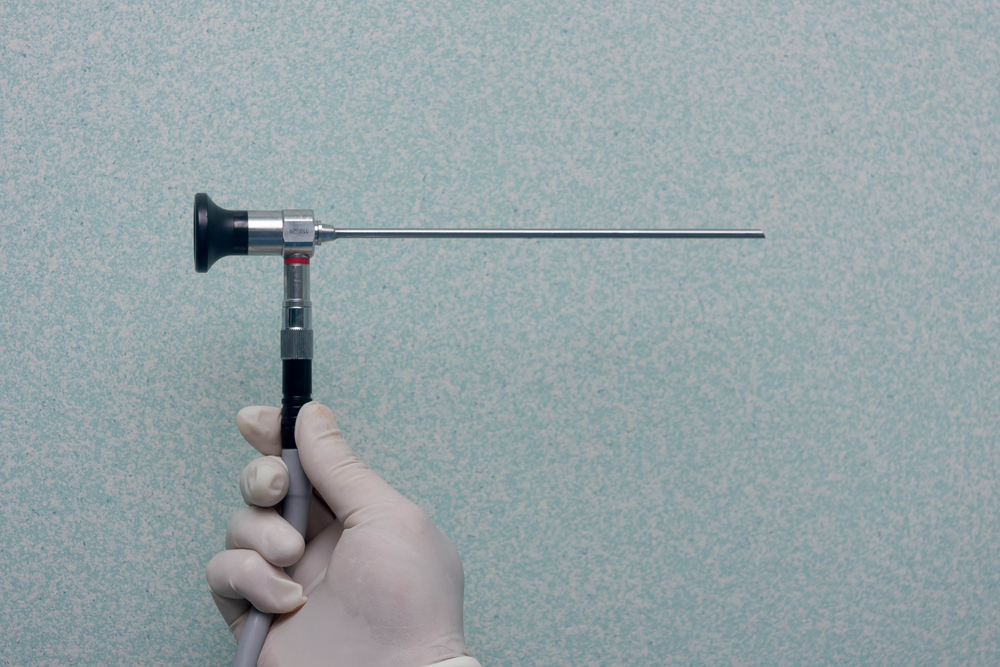

Después de que la anestesia haya sido aplicada, el cirujano hará pequeñas incisiones en la rodilla a través de las cuales bombeará solución salina para inflarla y lograr una mejor visibilidad.

Posteriormente introducirá un tubo estrecho con una cámara muy pequeña a través de una de las incisiones, de esta manera el cirujano podrá observar en la pantalla y diagnosticar el problema. En caso de que se requiera realizar algún tratamiento quirúrgico, el cirujano introducirá instrumentos diminutos a través de las incisiones para reparar la rodilla a través de cirugía artroscópica.

Finalmente el cirujano drenará la solución salina y cerrará las incisiones con suturas y las cubrirá con un apósito.

La artroscopia de rodilla suele durar entre 30 minutos y poco más de una hora.